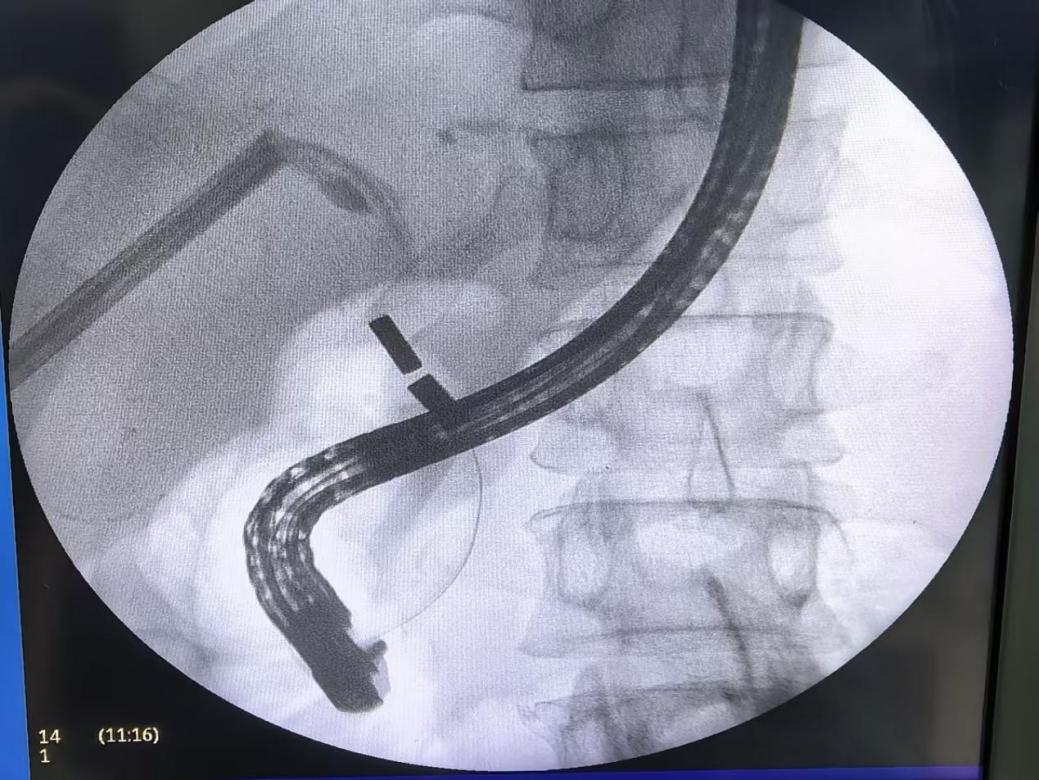

孙昊、李宇教授团队采用的磁疏通技术,创新性融合磁力学原理与微创操作,通过经皮肝穿刺胆道引流术(PTCD)和ERCP路径,将钕铁硼复合永磁体制成的子母磁体,分别送至梗阻胆道的近端与远端。异极磁力瞬间吸附实现组织“秒级吻合”,使梗阻部位组织受压坏死脱落,周围健康组织通过粘连修复形成光滑吻合口,最终实现胆道再通。整个过程无需传统针线缝合,手术时间缩短至传统术式的1/3,且对患者创伤极小。术后患者生命体征平稳,胆道梗阻症状迅速缓解,肝功能指标逐步恢复正常。